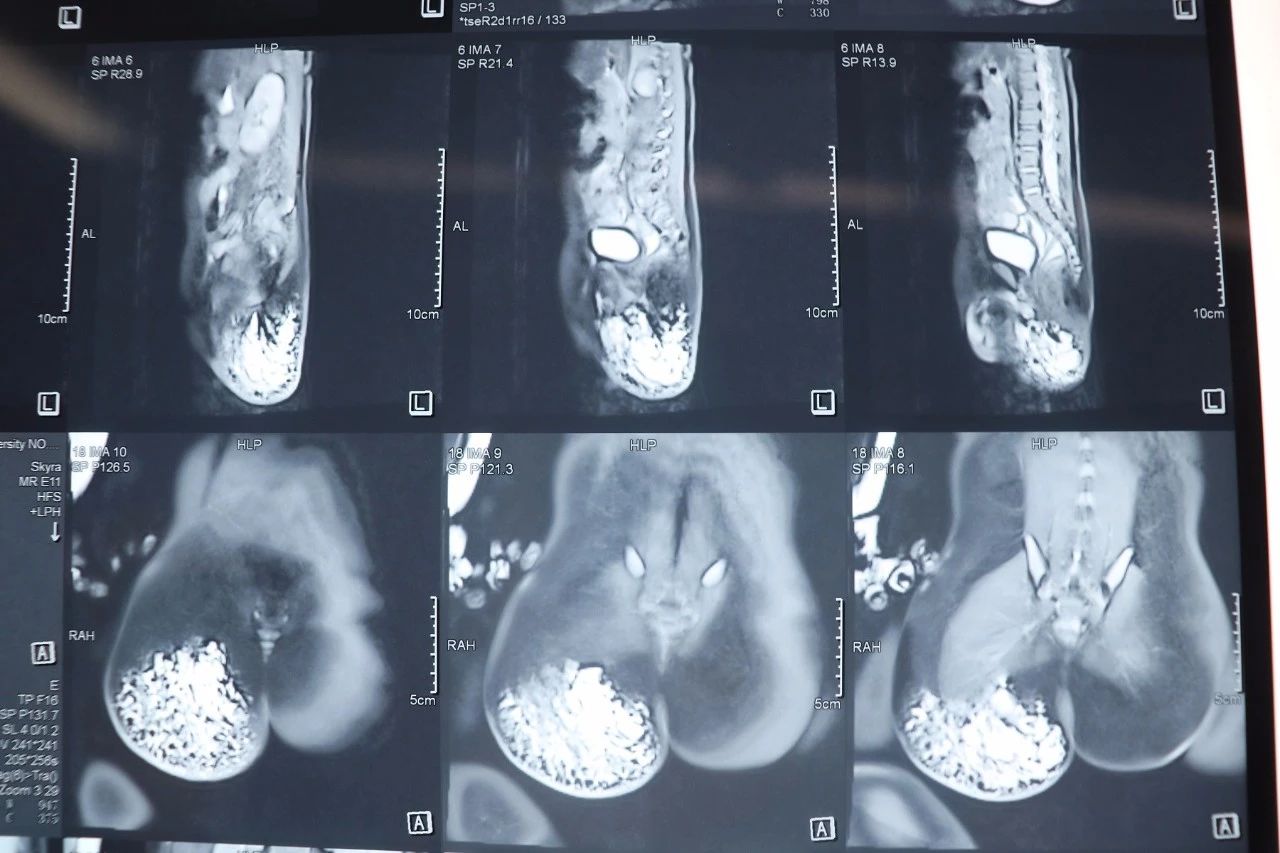

乔军波看到成成的磁共振检查时,就跟成成父母说孩子需要尽早手术治疗,不立即手术的话可能会出现严重的后果。因为,现在病变已经临近坐骨神经,也可能会侵犯肛门括约肌,造成大便*禁失**,病变持续长大,会侵犯整个阴囊。成成的父母也意识到孩子疾病的严重性,同意立刻手术,于是经过一系列术前准备之后,一场精细而又紧张的手术开始了。

术中发现,右臀部肛周阴囊会阴部肿块,为畸形淋巴血管团块,大小约10*8*6cm,内可见部分凝血块,病变主要累及皮肤、皮下脂肪、深筋膜、臀大肌、臀中肌、臀小肌、梨状肌、肛门括约肌、臀上神经、臀下神经、皮神经,病变侵犯阴囊与肛门连接处,紧邻坐骨神经,上至骶骨下端,最深至坐骨结节,术中,乔军波小心分离,保护坐骨神经、臀上、下神经,以避免损伤,切除肛周病变及部分肛门括约肌后,行肛门括约肌修复重建术,以避免术后大便*禁失**。